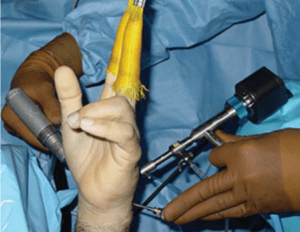

Common Conditions of the Hand